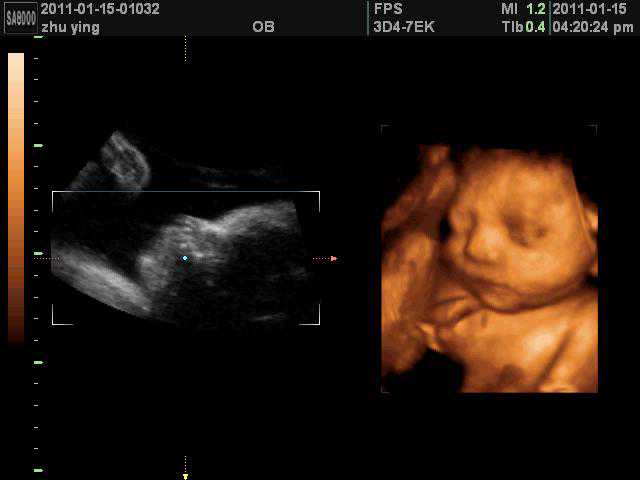

最后来个可爱的四维照!

有没有觉可爱到爆!